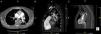

A central bilateral intraluminal filling defect (arrows) is seen, consistent with pulmonary emboli (A – transaxial view; B and C – sagittal views). A thromboembolus (arrowhead) is also seen in the right atrium (C). IVC: inferior vena cava; LV: left ventricle; RA: right atrium; RV: right ventricle; SVC: superior vena cava.